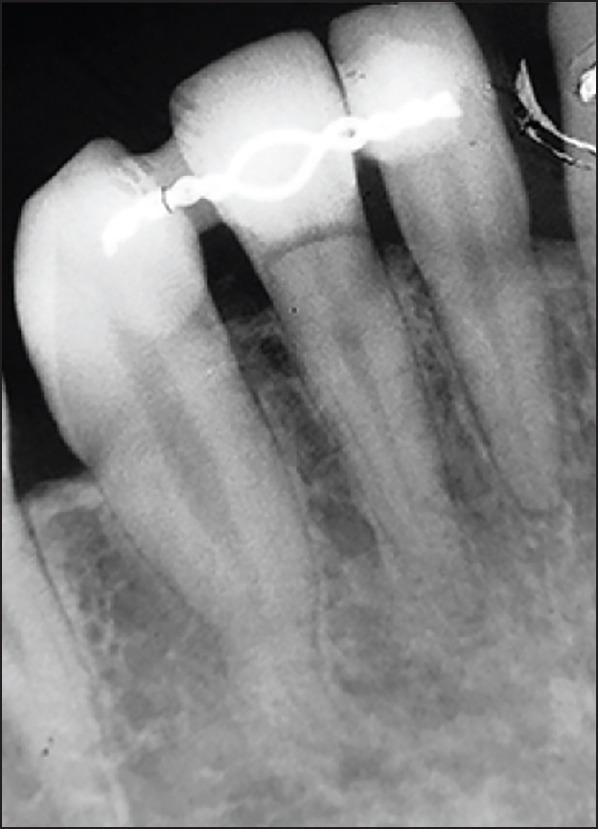

This case report describes the treatment of a double root fracture of a lateral mandibular incisor and its follow- up over 3.5 years. The reason for the consultation was a tooth mobility following a fall that had occurred 2 days earlier. A test of pulp vitality for tooth 42 was positive. Periodontal probing at the level of the gingival sulcus confirmed the intactness of the epithelial attachment. Retro-alveolar radiographic examination revealed a double root fracture of tooth 42. A semi-rigid extra-coronal splinting was performed and a light grinding of the incisal edge of tooth 42 was then carried out in light of the dislocation of the coronal fragment, and the occlusion was checked with a strip of articulating paper. The outcomes at 6 months revealed that pulp vitality was still preserved, consolidation of the apical fracture had occurred, and the coronal root fracture was starting to heal. The 1-year, 2-year and 3-year follow ups revealed preserved pulp vitality, an absence of a fracture line in apical images, and no root resorption. This case report provides evidence for the preservation of vitality in the setting of a double root fracture.

本病例报告描述了一例下颌侧切牙双根骨折的治疗及其3.5年的随访情况。会诊原因是2天前摔倒后牙齿松动。对42号牙的牙髓活力测试呈阳性。在龈沟水平进行牙周探诊证实上皮附着完整。牙槽后位X线检查显示42号牙双根骨折。进行了半刚性冠外夹板固定,然后根据冠部骨折块的移位情况对42号牙的切缘进行了轻度打磨,并用一条咬合纸检查了咬合情况。6个月时的结果显示牙髓活力仍然保留,根尖骨折已愈合,冠根骨折开始愈合。1年、2年和3年的随访显示牙髓活力保留,根尖影像中无骨折线,且无牙根吸收。本病例报告为双根骨折情况下保留牙髓活力提供了证据。